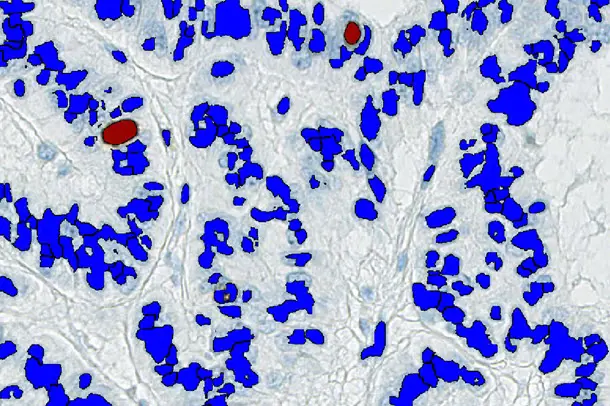

To perform conventional image analysis

This conventional image analysis application marks negative (=blue) and positive (=brown) tumour cells. It is easy to see that the demarcation of individual tumour cells does not work well.